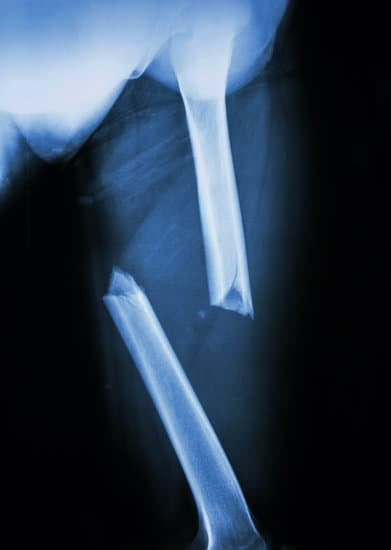

대퇴골 골절은 특히 노인 인구에서 발생률이 높은 중대한 부상으로, 이는 이동 능력에 심각한 영향을 미칠 수 있습니다.

이러한 골절은 낙상, 교통사고 또는 높은 에너지가 작용하는 다양한 사고로 인해 발생할 수 있습니다.

대퇴골 골절의 치료는 골절의 종류, 환자의 나이, 전반적인 건강 상태 및 골절이 발생한 대퇴골의 위치에 따라 달라질 수 있습니다.

대퇴골 내고정술은 대퇴골 골절의 치료를 위해 수행되는 수술 방법 중 하나로, 골절된 뼈 조각을 정렬하고 고정하기 위해 금속 임플란트를 사용합니다.

이 방법은 골절의 정확한 정렬을 유지하며, 골절 부위의 안정성을 보장하고, 치유 과정을 촉진하는 데 도움을 줍니다.

대퇴골 내고정술은 특히 중단부 골절 또는 대퇴골 상부의 복잡한 골절에서 선호되는 방법입니다.